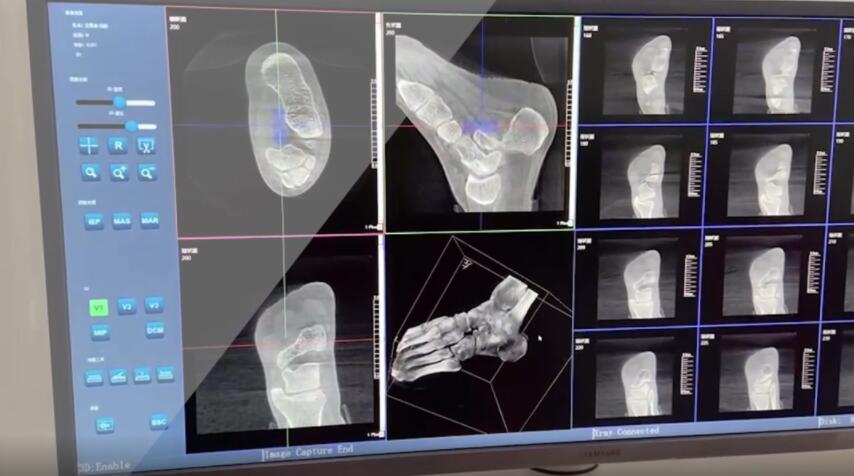

【醫(yī)療科普】:踝關(guān)節(jié)三維掃描

在術(shù)前,我們需要做三維掃描的CT檢查,我們必須要有CT的片子,還要有三維的重建。

在術(shù)中,我們?cè)趺慈ヅ袛嚓P(guān)節(jié)面平不平整呢?常規(guī)的正側(cè)位影像是不能判斷的。有些醫(yī)生為了準(zhǔn)確的判斷,可能會(huì)選擇做開(kāi)放性的手術(shù),把關(guān)節(jié)暴露出來(lái),在眼睛的直視下判斷關(guān)節(jié)面平不平整。但是關(guān)節(jié)全部打開(kāi),無(wú)疑增加了病人的創(chuàng)傷,而且增加了患者的恢復(fù)時(shí)間。所以如果在術(shù)中我們有三維影像的支持,對(duì)醫(yī)生做手術(shù)而言就會(huì)事半功倍,而且能夠大大的增加手術(shù)準(zhǔn)確度,增加患者術(shù)后的預(yù)后。所以在術(shù)中有三維影像的支持是非常必要的!

三維影像 看透關(guān)節(jié)內(nèi)骨折的“眼睛”